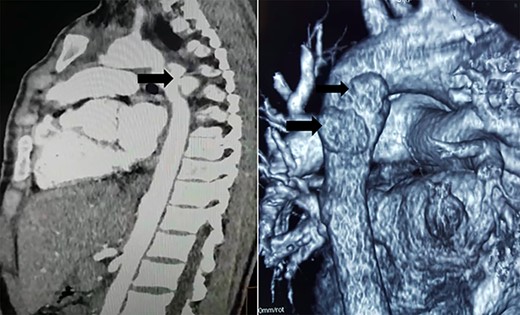

Computed tomography (CT) scan showed two mycotic pseudoaneurysms of the descending aorta (Fig. 3).

CT scan showing two mycotic pseudoaneurysms of the descending aorta.